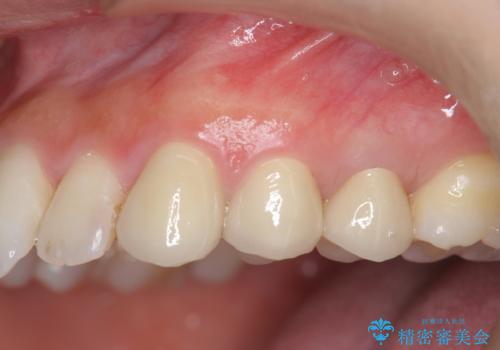

- 歯ぐきの腫れや、歯の内部が黒く見えることからの虫歯の治療を求めて来院されました。

虫歯が大きかったことから、神経の温存はできたものの歯ぐきよりも深い虫歯の問題を解決するため部分矯正治療を併用したセラミック治療を行うこととしました。

当初、歯ぐきよりも深い虫歯のぞんざいや、歯のポジションに問題がありましたがマルチブラケットを用いた部分矯正を行うことで適切な位置へと歯を移動させ、歯周環境を整えたセラミック治療を行うことができました。